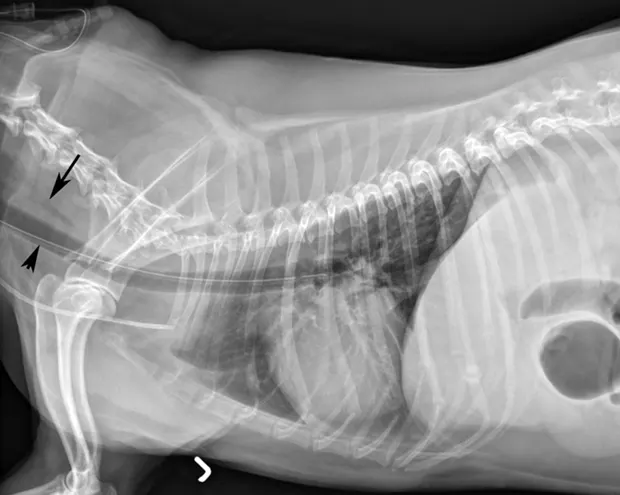

If placement is uncertain, infuse a small amount of nonionic contrast material to differentiate the esophagostomy tube from the endotracheal tube or jugular catheter (B).

If the tube is in the trachea, the portion running in the proximal cervical region will be visibly ventral to the esophagus on radiography (C).